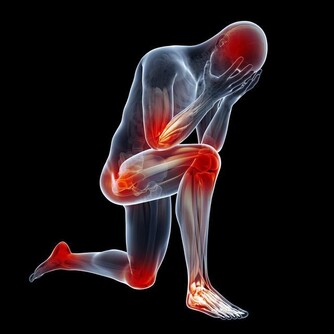

2、會陰疼痛

隨著癌細胞的轉移,前列腺癌患者會出現持續性的腰痛,還有會陰疼痛等。臥床時更為劇烈。

髖骨,胸腰椎是前列腺癌轉移的好發部位。常會有持續性,間歇性的疼痛,也有的人與有遊走的疼痛。

3、腰部酸脹

因為前列腺癌的發展,影響膀胱或者輸尿管,出現腎積水,喊著有要不的酸脹感。